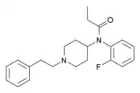

Chemical structures of various fentanyl analogues

Orthofluorofentanyl | N-(2-Fluorophenyl)-N-[1-(2-phenylethyl)-4-piperidinyl]-propanamide | 910616-29-4 |

|

2-Fluorobutyrfentanyl (o-FBF) | N-(2-Fluorophenyl)-N-[1-(2-phenylethyl)-4-piperidinyl]-butanamide | 2163847-76-3 |

|